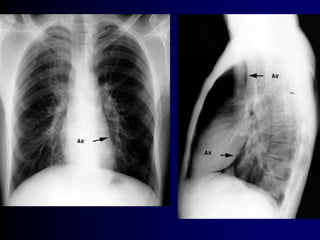

1-Year Therapy With MFNS Did Not Induce

Nasal Atrophy in Patients With PAR1,a

Nasal Biopsies

Before MFNS Treatment After 12 Months of Treatment With

MFNS 200 µg/d

Disruption of epithelium

Eosinophil infiltration

Epithelium intact

No eosinophil infiltration

aThe clinicalrelevance ofthese data in the treatmentofallergic rhinitis is notknown.

MFNS = mometasone furoate nasalspray;PAR= perennialallergic rhinitis.

1. Minshall E et al. Otolaryngol Head Neck Surg. 1998;118:648–654.